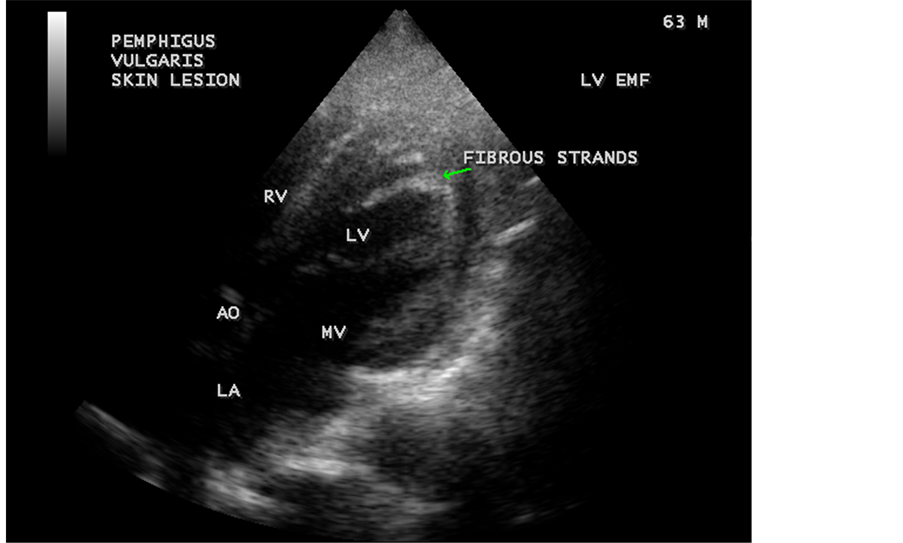

Figure 40. Left ventricular endomyocardial fibrosis in Pemphigus skin lesions in a 63-year-old male. (Pemphigus is an autoimmune blistering disease of skin and mucous membranes, characterized by intraepidermal blisters and immunologically mediated by circulating immunoglobulin G autoantibodies directed against the keratinocyte cell surfaces. Therapy is directed to reduce inflammation and antibody production by corticosteroids and immunosuppressants).

3.4. Screening of Population